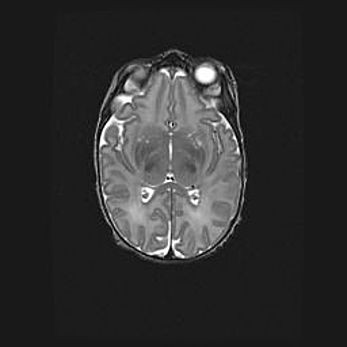

Множественные мелкие кисты перивентрикулярной области.

Киста прозрачной перегородки.

Возраст: 28 дней

Вес: 2400 г

Пол: женский

Окружность головы: 33 см

Срок гестации: 34 недели

Перивентрикулярная киста – это полостное образование в околожелудочковых областях белового вещества головного мозга. С морфологической точки зрения – это мелкоочаговая зона коагуляционного некроза, возникшая после инфаркта белого вещества. Наиболее часто поражаются начальные отделы задних рогов боковых желудочков. Обычно образования заполнены жидкостным содержимым.

Киста прозрачной перегородки может располагаться в переднем отделе межжелудочковой перегородки, в области мозолистого тела и мозжечка.